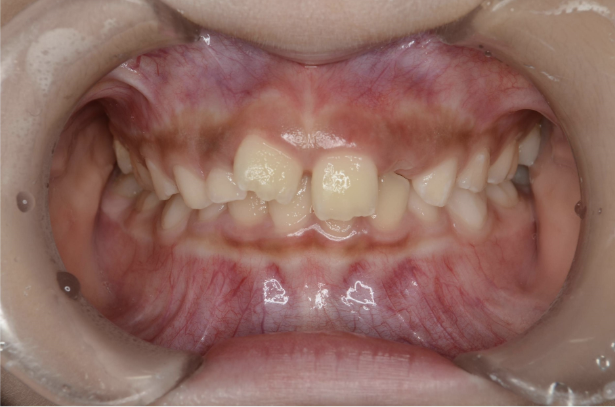

お子さんが「矯正治療」をはじめる時に直面する問題は 「装置が目立つ」、 そして「歯を抜く」ことがあげられます。

10歳を超えてからの治療開始ではそのようにならざるを得ないことが多いのです。

しかしながら、5〜7歳頃に治療をスタートすれば 目立ちにくい装置で、歯を抜かずに治療できることがあります。

また5〜7歳頃から治療を開始すると、骨格を改善することが可能です。

骨格が改善されるとお顔つきが良くなることが期待できます。

歯並びが悪いのは、あごの骨が成長不足で小さいことで起こります。 当院で行なっているこどもの歯ならび治療はあごの骨に働きかけることができます。 骨に働きかけることで成長不足のお子さんの骨が成長して、顔つきが良い方向に変わっていく可能性があります。 実は大きくなってからの矯正治療は歯が並んでいるだけで骨やお顔つきは変わっていないのです。 5〜7歳ぐらいで治療を開始すると成長不足の骨に働きかけて、より良い顔つきになれる可能性があります。

※治療結果には個人差があります。